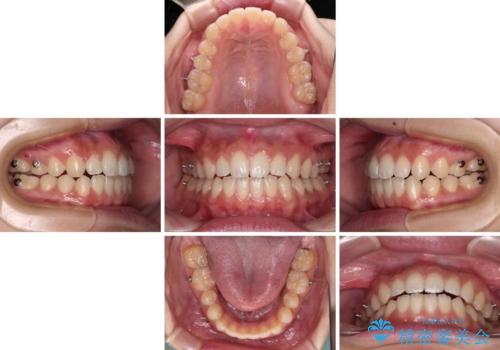

- インビザライン

- 治療期間

- 1年10ヶ月

- 治療回数

- 10-30回